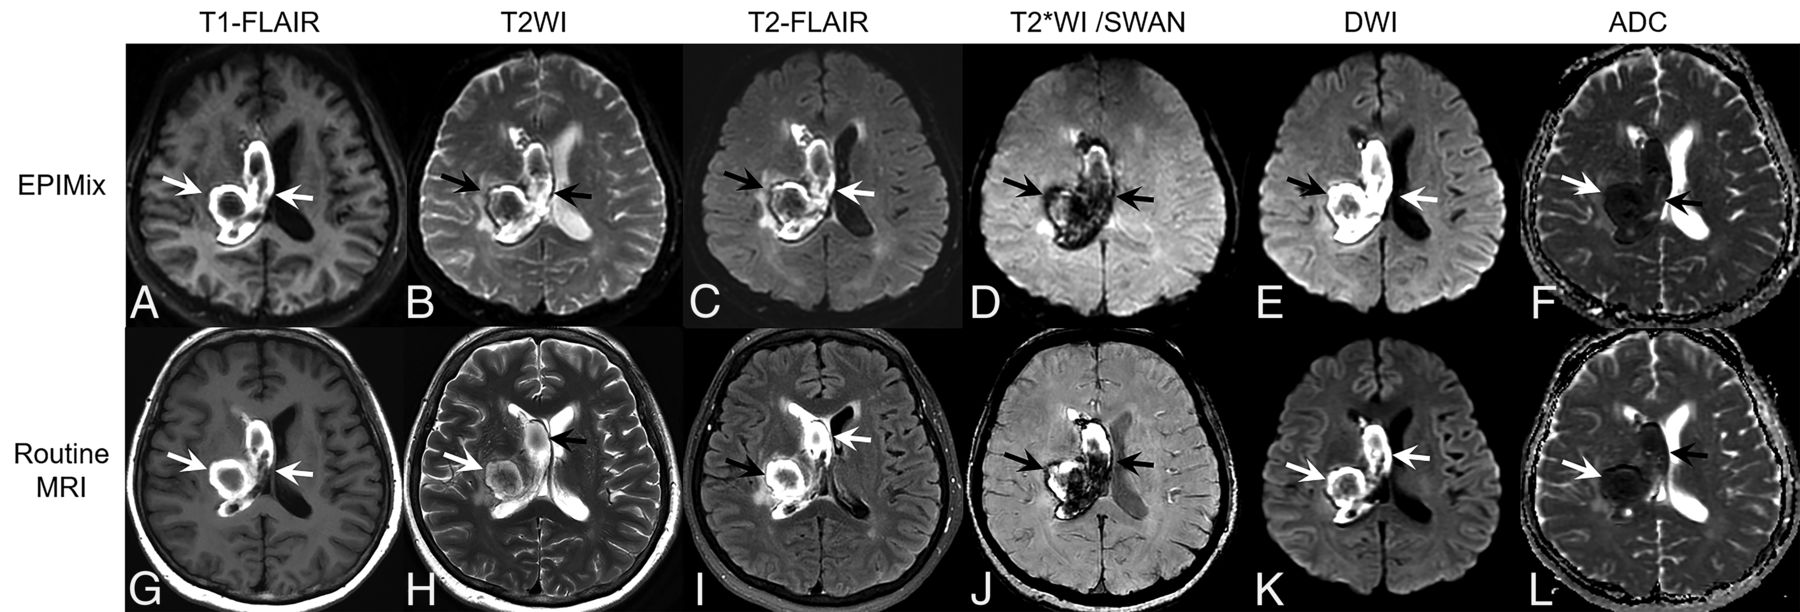

A 59-year-old woman with intracranial hemorrhage. A right thalamic hemorrhage with intraventricular extension to the right lateral ventricle shows mainly hyperintensity on T1-FLAIR (A and G), hyperintensity on T2WI (B and H) and T2-FLAIR (C and I), blooming artifacts on T2*WI (D) and SWAN (J), and diffusion restriction on DWI (E and K) (arrows in each sequence). These findings are well-visualized on both EPIMix MR imaging (A–F) and routine MR imaging (G–L).